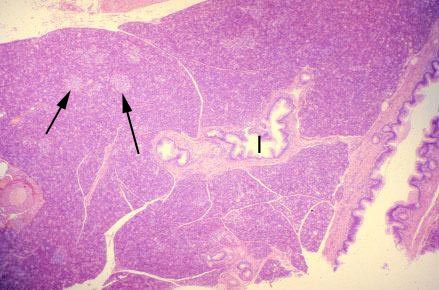

VIII-21, Slide 68, Pancreas (H&E). Low power view of pancreas. The majority of cells are basophilic-staining serous acinar cells. The islets of Langerhans (arrows) are pale-staining clusters of cells. Note the interlobular ducts (I) located within a connective tissue septum.